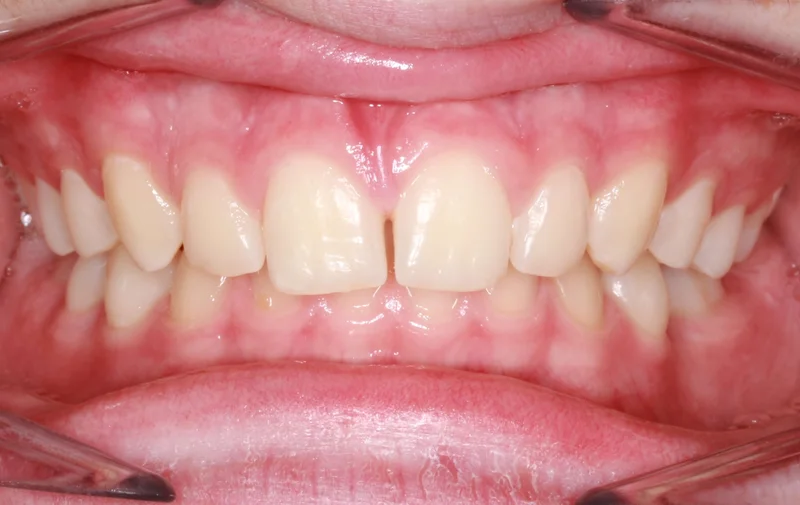

Center Bite

Center Bite - Before Treatment

Before

Center Bite - After Treatment

After